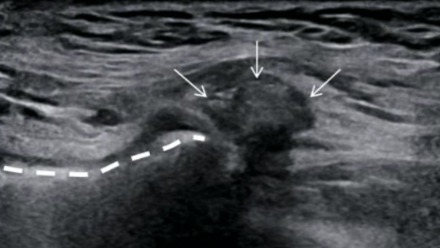

Hernie inguinale indirecte

Hernie inguinale directe

Coupe sagittale

- Confirme l’hernie

- Mesure le collet